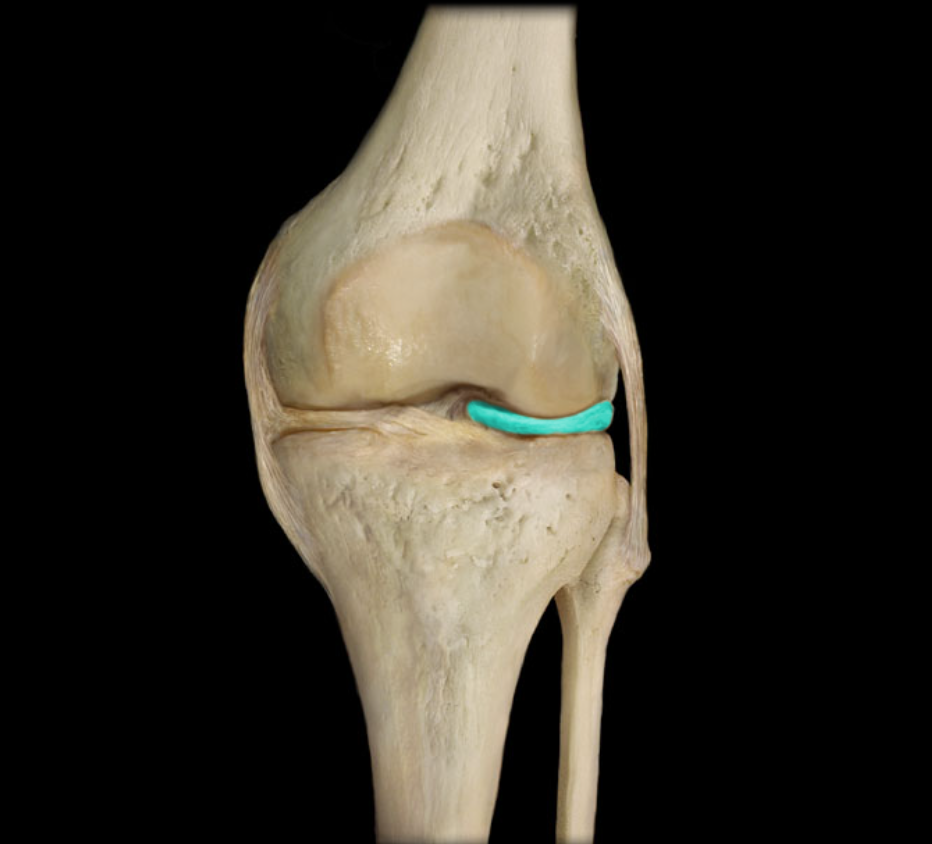

Lateral meniscus